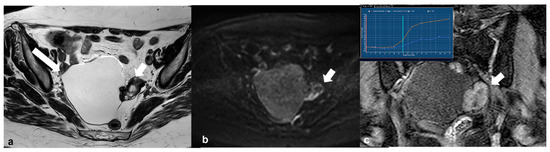

2.5.2. Decidualized Endometrioma